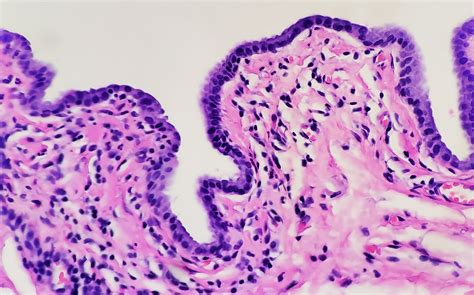

• gartner's duct cyst pathology

• gartner's duct cyst pathology outlines